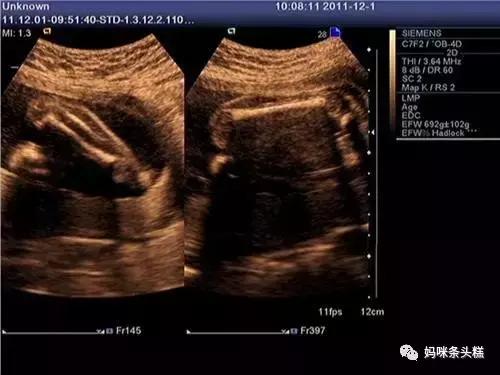

二维彩超是一种类似切面图的视觉效果;

三维则是在二维的基础上,立体图的视觉效果,但画面是相对静态的;

四维除了具备三维的立体以外,还具备立体画面的连续性观看,也就是将看到的多个三维立体视觉图连续起来,完全可以看到宝宝在腹中立体动态的效果;

三类B超均有不同的优势,目前也仍有延续用二维彩超仔细查看孩子内部器官切面发育是否正常的临床做法,因此不能完全说四维就一定好,二维就不可取,在临床上医生都会运用适宜的手段进行孕检,确保宝宝健康出生。